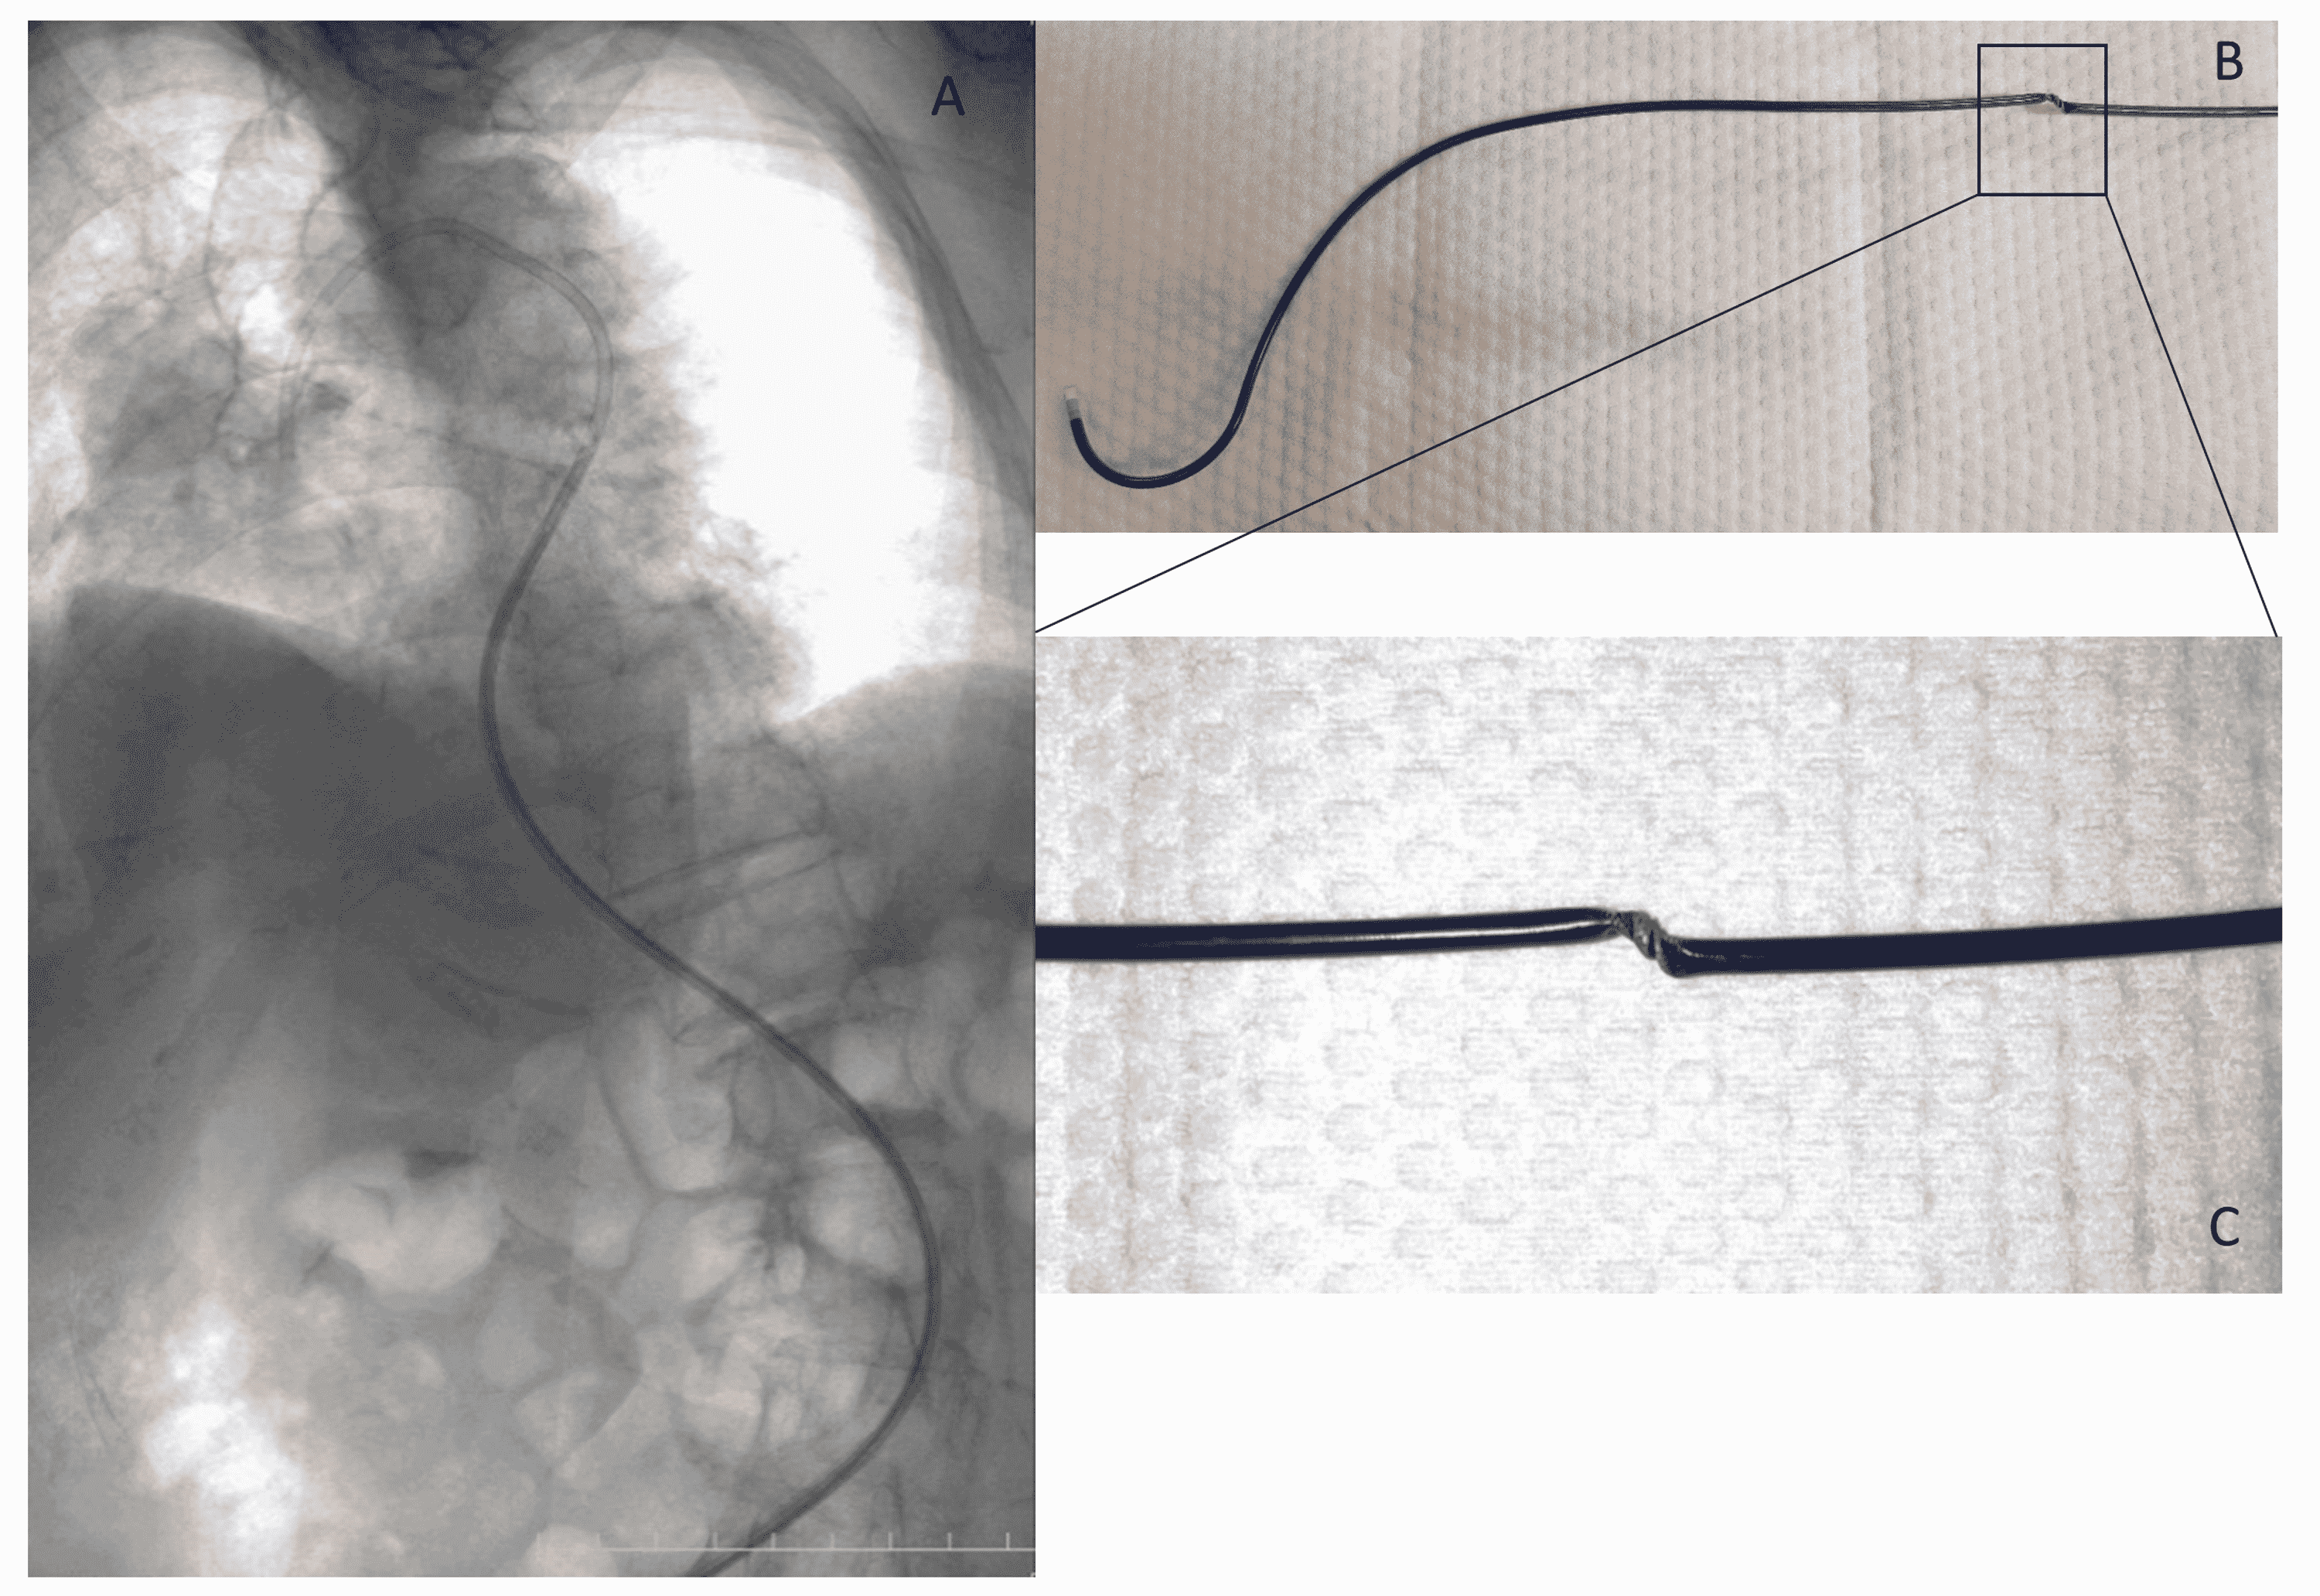

Guiding catheter (EBU) entrapped in right subclavian artery YouTube Ebu Guide Catheter Full Form A guide catheter with a supportive shape should be used, such as the voda/ebu/xb catheters for the left coronary artery, amplatz left. Usual guiding catheters, but adapted to have a good support and specific manipulation to ostial cannulation. 90°), and a reinforced construction (3 vs. An effective and easy manipulate method is introduced with ebu guiding catheter (gc) in this. Ebu Guide Catheter Full Form.